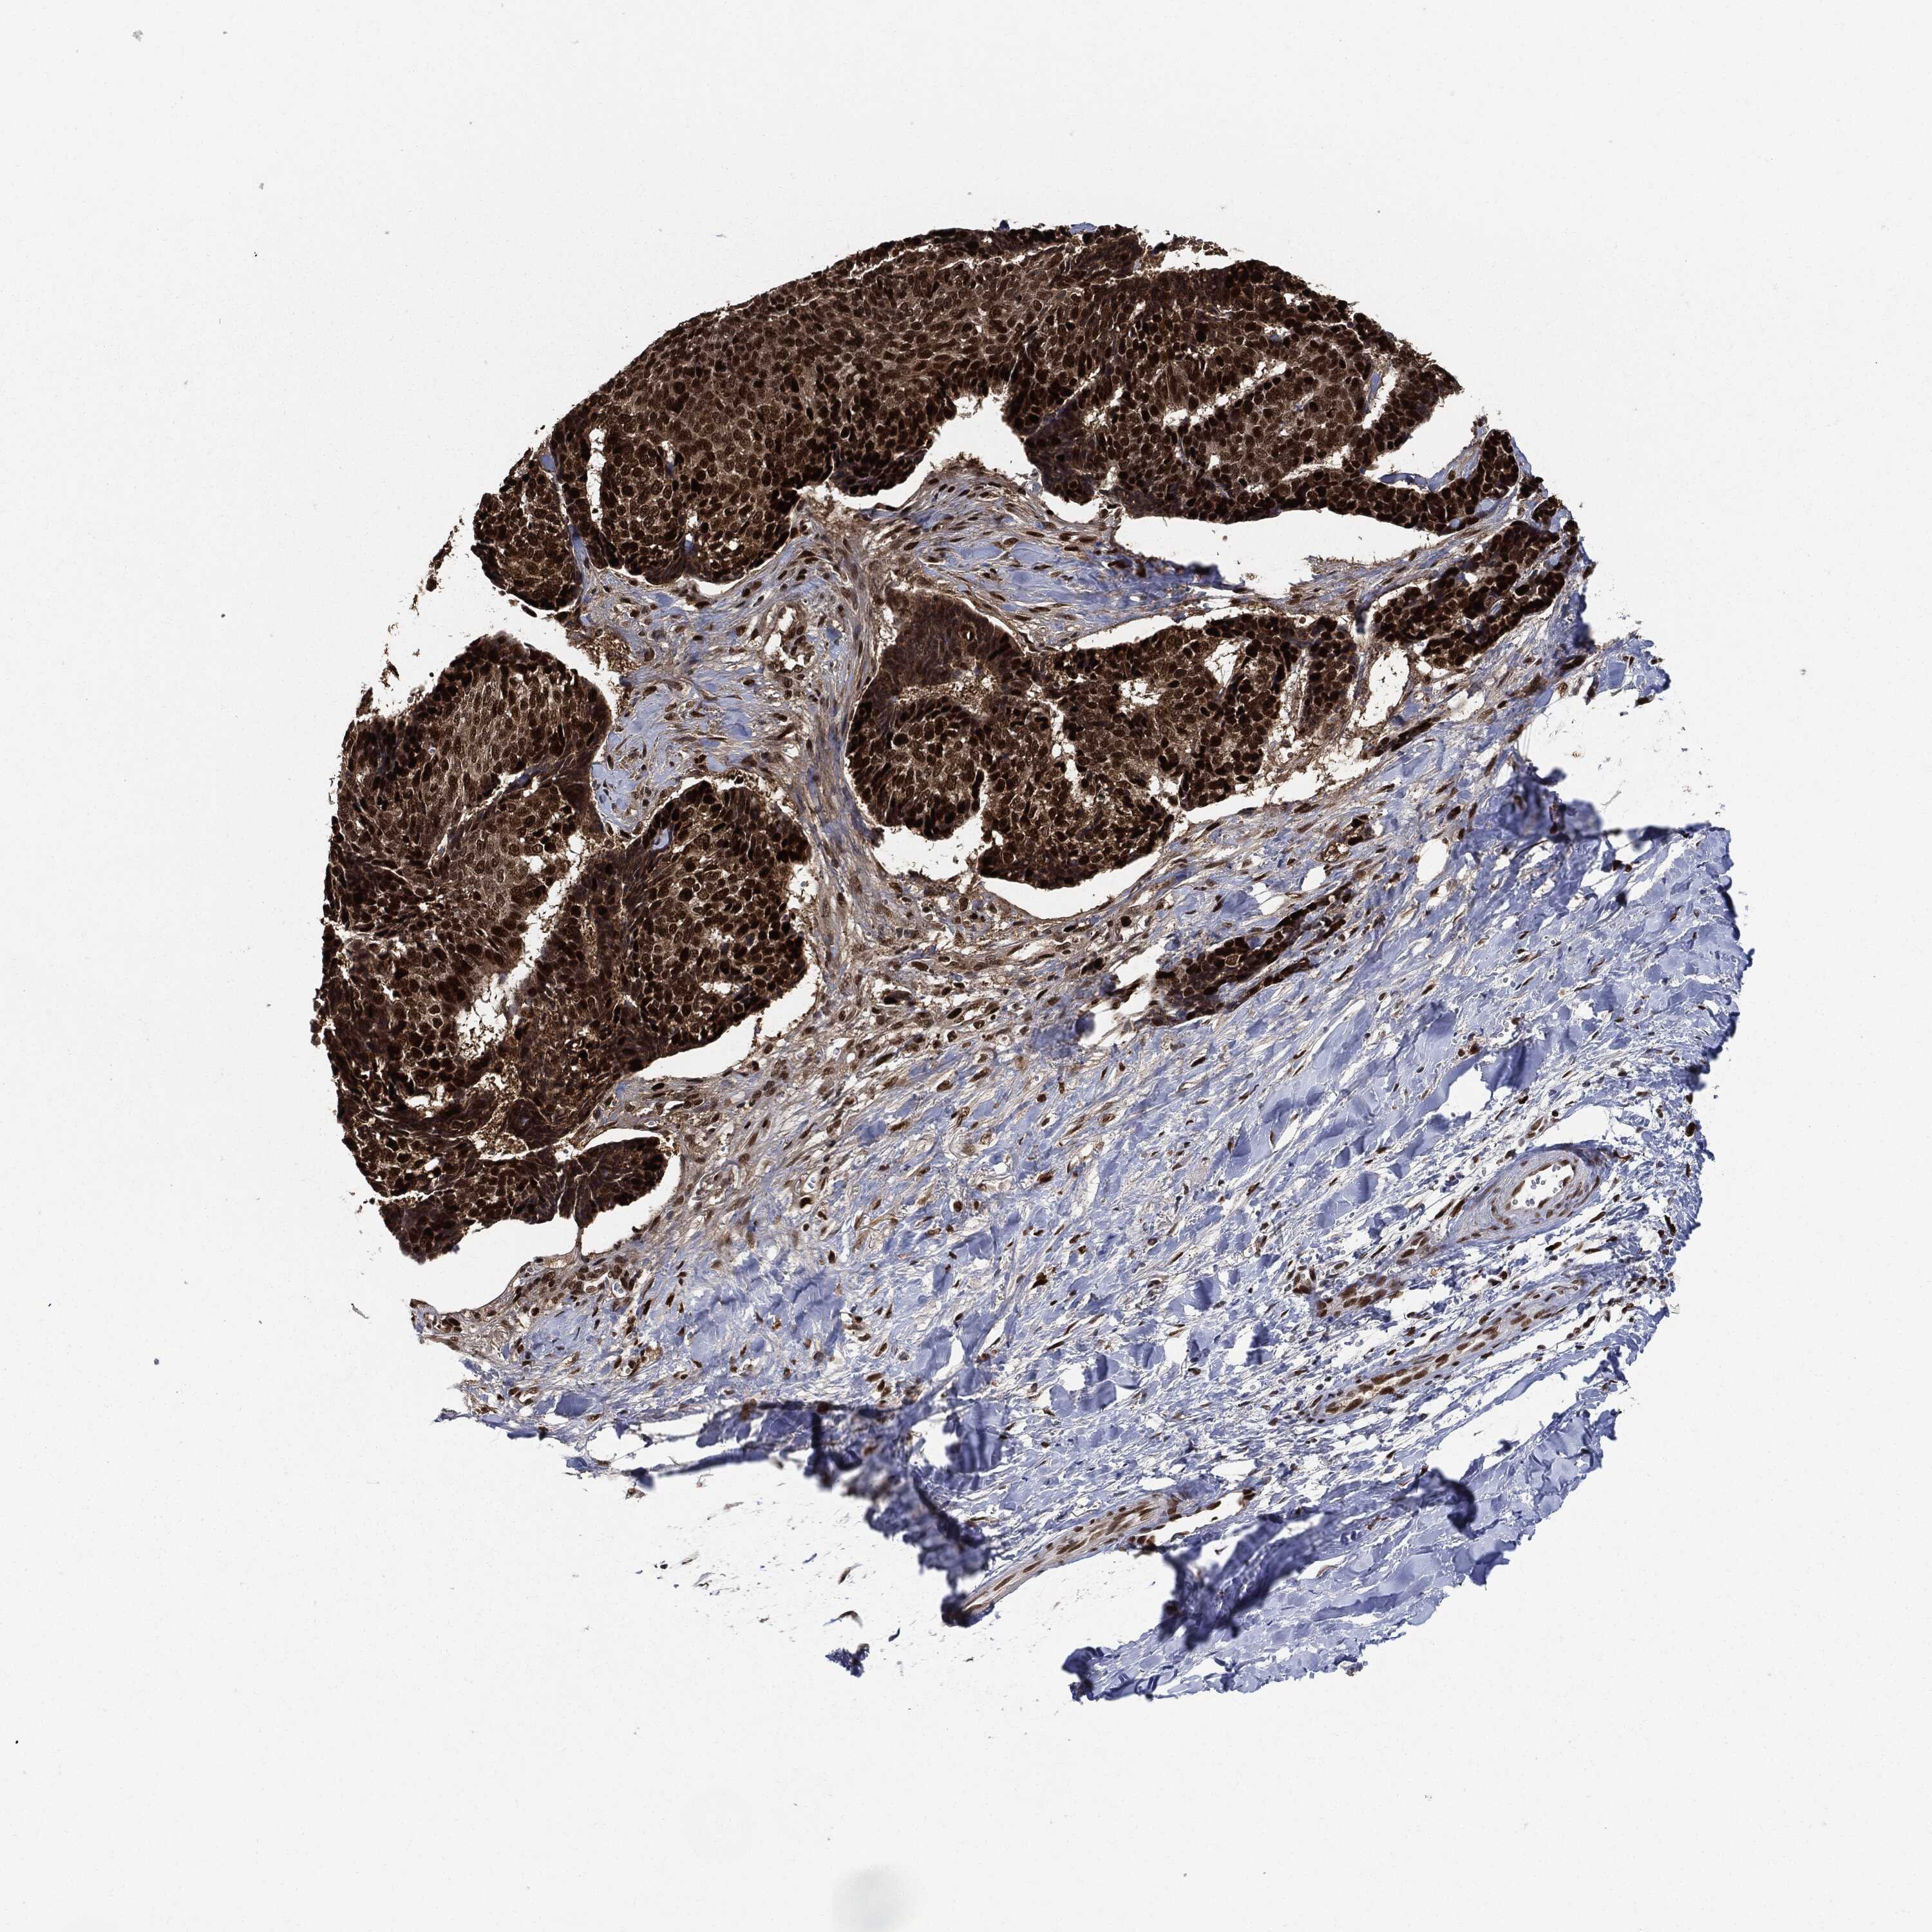

SKIN CANCER - Protein expressioni

A mouse-over function shows sample information and annotation data. Click on an image to view it in a full screen mode. Samples can be filtered based on level of antibody staining by selecting one or several of the following categories: high, medium, low and not detected. The assay and annotation is described here.

Antibody stainingi

Antibody staining in the annotated cell types in the current human tissue is reported as not detected, low, medium, or high, based on conventional immunohistochemistry profiling in selected tissues. This score is based on the combination of the staining intensity and fraction of stained cells.

Each image is clickable and will lead to virtual microscopy that enables deeper exploration of all samples and also displays staining intensity scores, fraction scores and subcellular localization as well as patient and tissue information for each sample.

HPA030521

HPA030522

HPA030523

CAB000148

CAB080240

CAB080241

CAB080242

Staining

High

Medium

Low

Not detected

Intensity

Strong

Moderate

Weak

Negative

Quantity

>75%

75%-25%

<25%

None

Location

Nuclear

Cytoplasmic/membranous

Cytoplasmic/membranous,nuclear

Basal cell carcinoma

Squamous cell carcinoma, NOS

Squamous cell carcinoma, metastatic, NOS